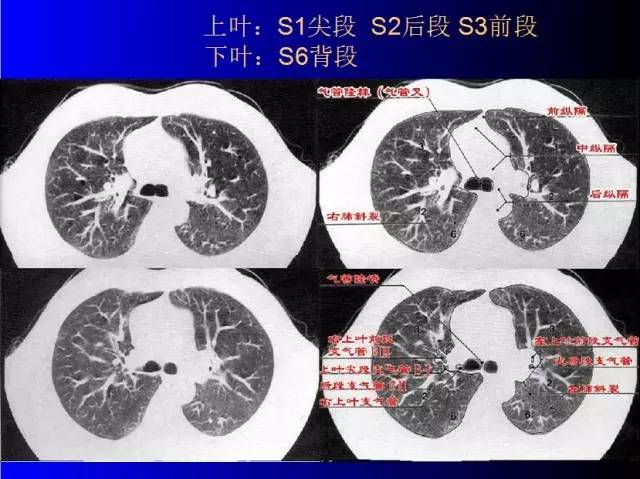

肺部基础X片及CT片解读